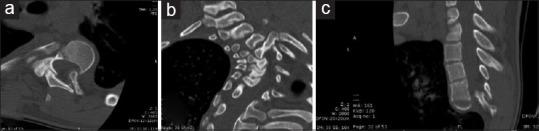

Ten patients were diagnosed with scoliosis in neurofibromatosis type I aged between 8 and 25 years, Cobb angle of the thoracic curve >45°, and minimum follow-up (FU) of 1 year and treated with posterior-only approach with third-generation high-density instrumentations. Radiographic measurements were performed on the coronal and sagittal planes. Nonparametric tests (Friedman test and Wilcoxon test) were applied to evaluate the reducibility of the preoperative curve (T0), the postoperative surgical correction (T1), and its maintenance on FU.

Statistics showed results compared to those evaluated in the literature with a combined approach regarding surgical correction and its maintenance on FU. On T1, a median correction of 53.5% of the scoliotic curve and of 33.7% of the thoracic hyperkyphosis was observed. On FU, the correction was maintained. A global improvement in balance was appreciated. The curves, despite rigid, showed a relative reducibility to bending tests and traction. No significant complications occurred.

10例年龄在8至25岁之间、胸弯Cobb角>45°且最短随访1年的Ⅰ型神经纤维瘤病脊柱侧弯患者,采用第三代高密度器械单纯后路手术治疗。在冠状面和矢状面上进行影像学测量。应用非参数检验(Friedman检验和Wilcoxon检验)评估术前侧弯(T0)的可矫正性、术后手术矫正(T1)及其在随访期的维持情况。

统计学结果显示,与文献中联合手术方法评估的手术矫正及其在随访期的维持情况相比,在T1时,观察到脊柱侧弯曲线中位数矫正53.5%,胸椎后凸矫正33.7%。在随访期,矫正得以维持。整体平衡得到改善。尽管侧弯僵硬,但在弯曲试验和牵引时显示出相对可矫正性。未发生明显并发症。